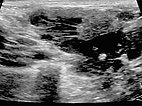

In der B-Bild-Sonographie (Längsschnitt) zeigt sich die venöse Malformation relativ homogen echoarm bis echofrei. Die venösen dysplastischen Gefäßkanäle sind mit dem Schallkopf kompressibel und enthalten flüssiges Blut.